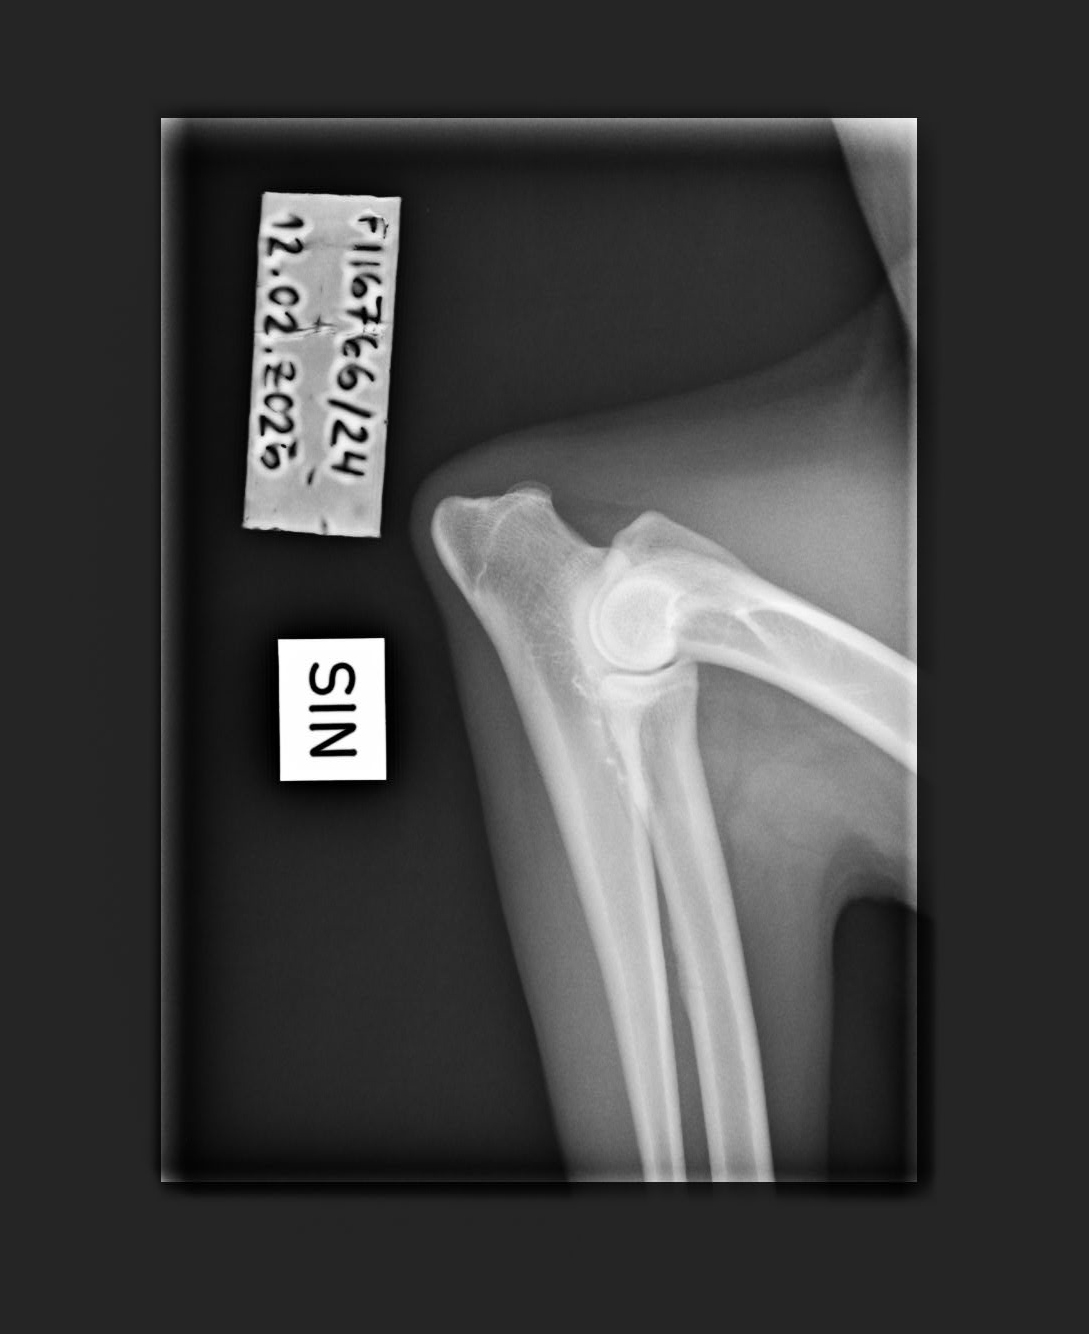

1/0 (see Notes) |

- Finnish Kennel Club's elbow x-ray report Dec '25: Signs suggestive of medial coronoid disease; further information about the condition of the joints can be obtained, if necessary, by computed tomography (CT) examination

- Finnish Kennel Club's elbow CT report Feb '26: A small amount of new bone formation around the medial coronoid process of the left elbow

- Elbow x-rays '11: left/right

- Elbow x-rays '12: left/right